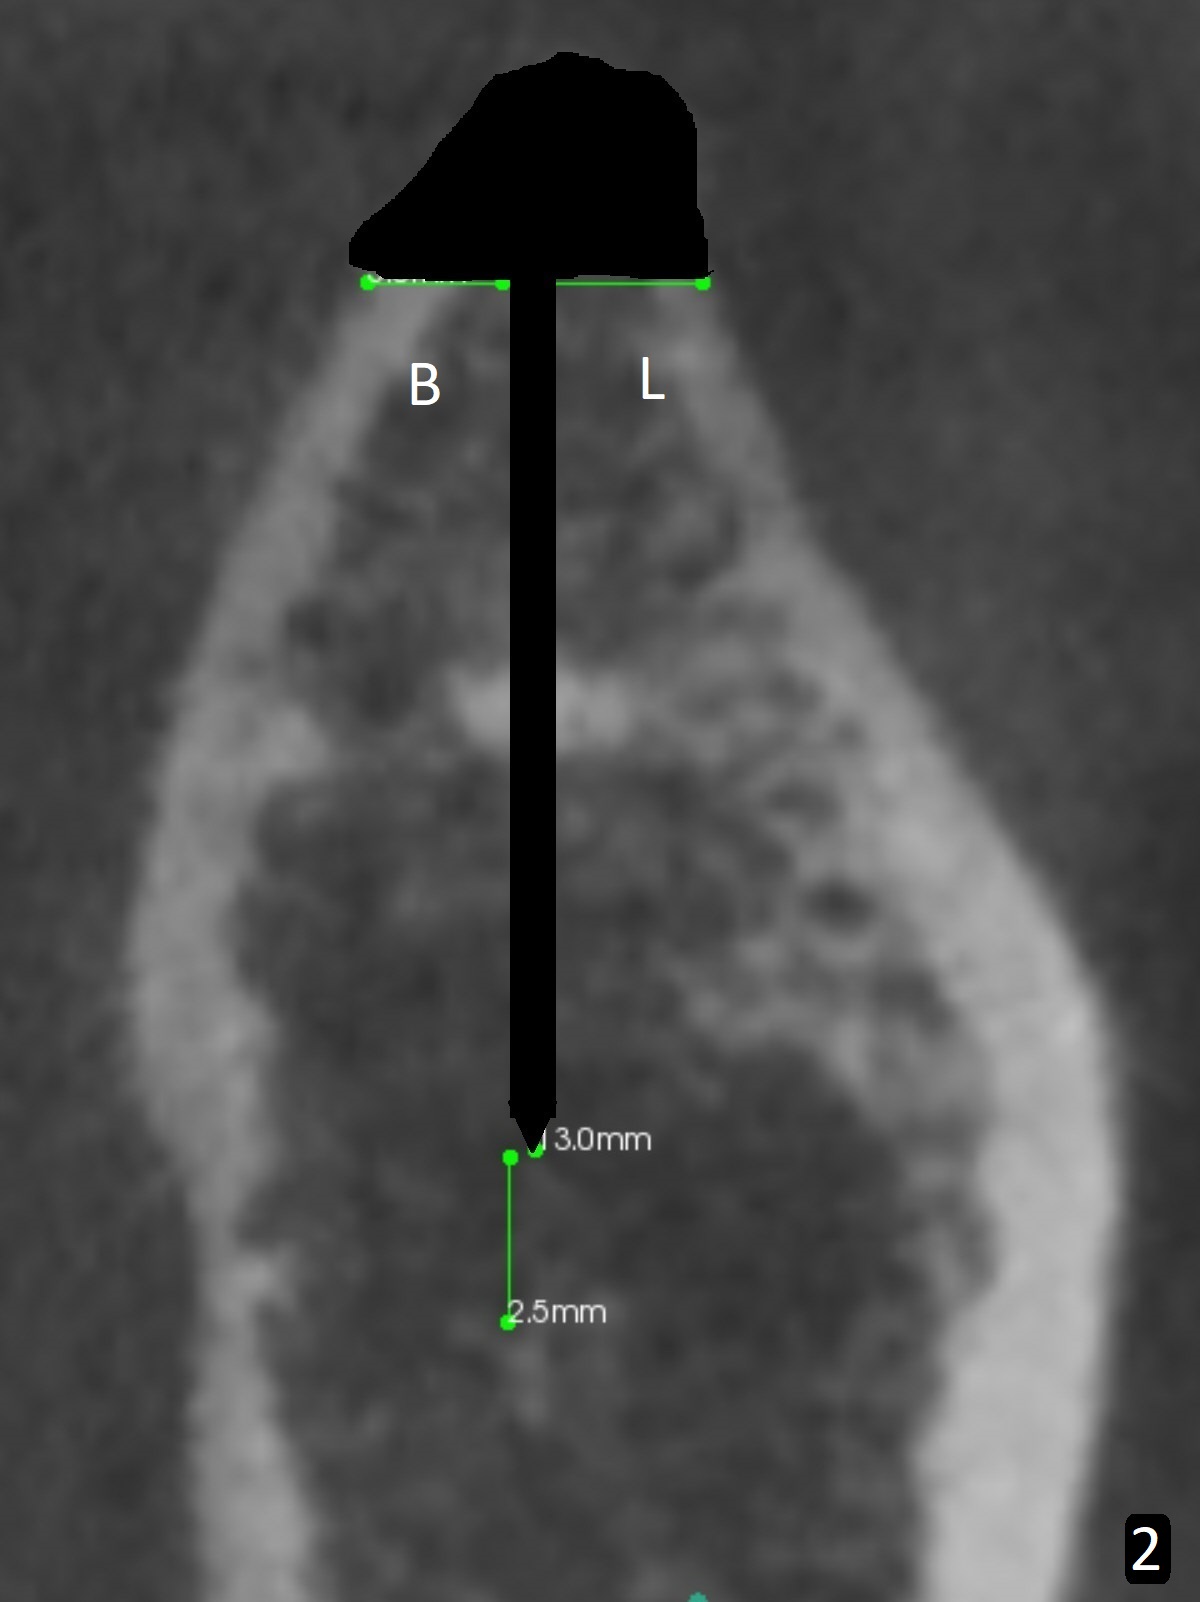

After incision over the narrow ridge at #30 (Fig.1) and ridge reduction (Fig.2 black area on the top; Fig.4 arrowheads), a 1.6 mm drill is used (Fig.2 (CBCT coronal section) long vertical black area) to start BEB (bone expansion and Bending). It is expected that the cortical and cancellous bone of the buccal (B) and lingual (L) plates can be expanded after use of Magic Expanders (ME) and 1.6 mm drill alternatively. In fact it appears that only the cancellous bone is pushed after MEs from 3 to 4.3 mm (Fig.3 arrows). There is no apparent cortical bone bending. There may be cancellous bone condensation. Dummy (Fig.4) and definitive (Fig.5) implants (4x11 mm) are placed. Since torque is 20 Ncm, a 5.5x4 mm healing abutment is placed (Fig.5,6 H). The opposing tooth is supraerupted; intrusion is pending. A 6x4(2) mm abutment is placed with a provisional 2 months postop. There is enough occlusal clearance. Impression is taken 5 months postop with difficulty because of subgingival margin (Fig.7). After cementation, the patient feels discomofort, which is relieved when the mesial embrasure is enlarged. Return to Lower Molar Immediate Implant, Armaments Xin Wei, DDS, PhD, MS 1st edition 12/14/2017, last revision 09/16/2018